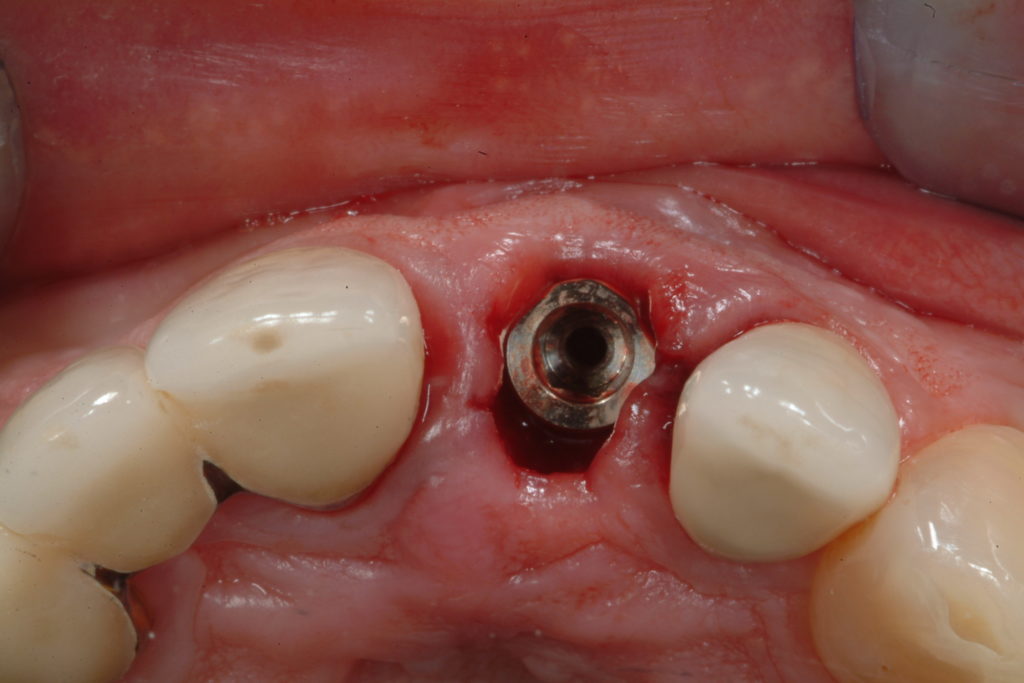

Immediate Loading: inserting the implant and tooth in the same session

As soon as the implant is inserted, the specialist assesses its primary stability and decides whether it is possible to already screw a temporary dental crown onto the implant in the same session.

The evaluation of the force with which the implant has entered the bone is expressed in newtons per cm2 and is generated by electronic measuring instruments.

Clinical case

Immediate post-extraction implant

In many cases, when an irrecoverable tooth is extracted, an implant can be immediately inserted, in the same session, without having to wait for the gum to heal and, therefore, avoiding additional surgery and anesthetic at a later date. This procedure is called Immediate post-extraction implant.

In various cases of post-extraction implants, immediate loading can also be carried out, when there are important aesthetic requirements, for example an incisor. the specialist will safely evaluate this possibility.

After the right amount of healing and stabilization time, the temporary crown is replaced with a more precise abutment and dental crown built by our laboratory, specialized in implant-prosthetics. These are customized and made in a way to be indistinguishable from the other natural teeth. The result is that the tooth has been replaced naturally, without damaging the neighbouring teeth and preventing bone resorption.